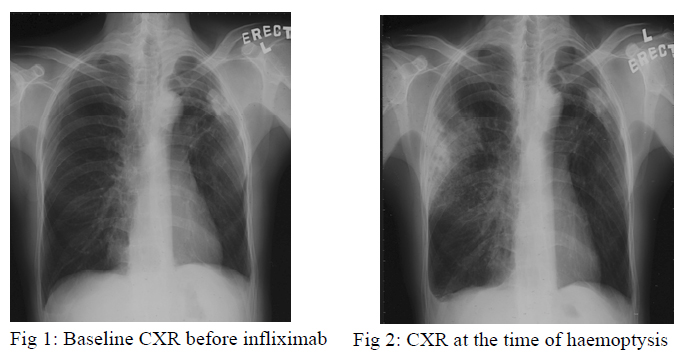

A 47-year old man, with past history of left pneumothorax over 20 years ago, suffered from ankylosing spondylitis for 10 years. Infliximab 800mg every fortnight was started since August, 2005 for treatment of ankylosing spondylitis. His baseline Mantoux test was negative but the chest radiograph, which had been taken before commencement of infliximab, showed a small opacity over the left upper lobe peripheral region (fig 1).

He developed haemoptysis 3 days after receiving the third dose of infliximab at the end of September 2005. There was no systemic symptom. Chest radiograph showed new consolidation at the right upper lobe and static size of the left upper zone opacity (fig 2). Blood tests revealed normal white cell count and raised ESR. Sputum smears for acid fast bacilli (AFB) were negative for three consecutive days and bacteria culture was negative. Infliximab was stopped. Flexible bronchoscopy was performed and bronchoalveolar lavage was negative for AFB smear and bacterial culture. A course of augmentin was given with no clinical or radiological improvement. Fine needle aspiration of left upper lobe consolidation revealed granulomatous inflammation but Zeihl-Neelsen stain and Grocott stain were negative for acid fast bacilli and fungus respectively. Empirical anti-tuberculosis treatment including rifampicin, isoniazid, ethambutol and pyrazinamide were started in early December, 2005.

Chest radiograph taken after 2 months of treatment showed resolved right upper lobe consolidation, fibrotic change of right upper lobe and the left upper lobe nodule was static in size (fig 3). However, sputum for fungal culture grew scedosporium apiospermum (fig 4,5). Flexible bronchoscopy was repeated and AFB smear and fungal culture were negative in bronchoalveolar lavage. Computed-tomography (CT) guided fine needle aspiration showed degenerated hyphae only. Patient still experienced haemoptysis intermittently but there was no sign of other organ involvement. Voriconazole was not started in view of localized disease and potential drug interaction with rifampicin.